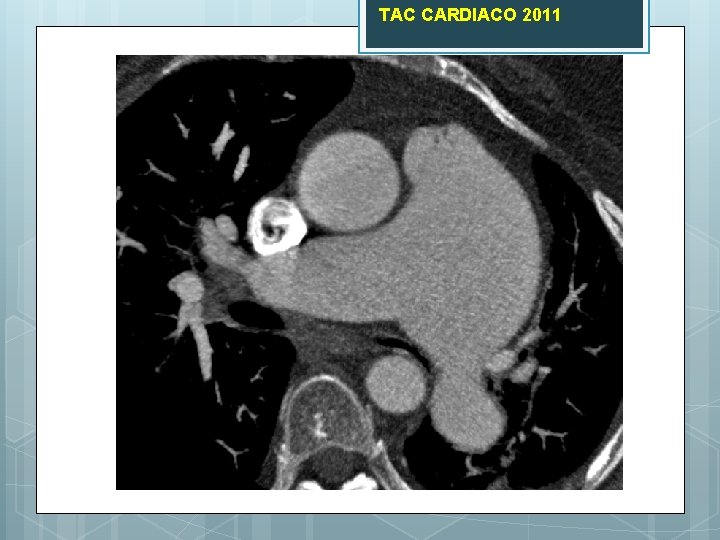

TAC CARDIACO 2011 Compresión bronquio izquierdo

TAC CARDIACO 2011 Compresión bronquio izquierdo Pérdida de volumen en pulmón izq

CATETERISMO 2011 Angiografía arteria pulmonar: Gran aneurisma de 59 x 71 mm en tronco pulmonar principal, en ÍNTIMO contacto con la bifurcación de la ACI, pero sin producir compresión en reposo.